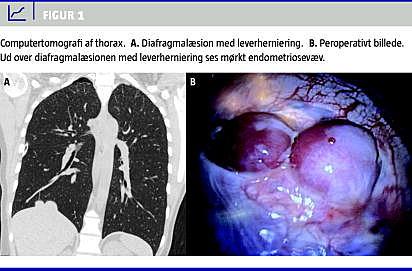

Efter flere tilfælde med basal højresidig spontan pneumothorax foretog man igen torakoskopi med henblik på basal pleurektomi. Man fandt nu et område på ca. 8 × 4 cm på diafragma med fenestrationer og diafragmaruptur med delvis herniering af leveren op i thorax. Desuden fandtes et mindre, mørkt område på diafragma (Figur 1 ). Man konverterede derfor til torakotomi, resecerede det mørke område og fenestrationerne på diafragma og foretog diafragmaplastik og basal pleurektomi. Histologisk blev der påvist endometriose i pleura parietale og det resecerede område af diafragma.

Det postoperative forløb var komplikationsfrit, og patienten havde på opgørelsestidspunktet været recidivfri i 12 måneder efter operationen. Ved en nærmere gennemgang af anamnesen kunne hun berette, at hun tidligere havde fået konstateret endometriose og var i fertilitetsbehandling. Hun havde selv bemærket en sammenhæng mellem menstruationscyklussen og de gentagne tilfælde af spontan pneumothorax, idet de hver gang opstod inden for de første 2-3 dage af menstruationen. Ved en nærmere gennemgang af patientens røntgenoptagelser kunne man nu genfinde den ved operationen fundne herniering af leveren (Figur 1).